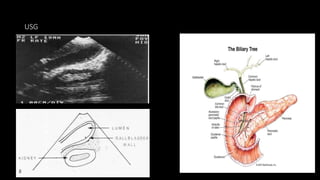

 Ultrasound : The mainstay of imaging in cholecystitis

• Gallbladder wall thickening (>3 mm), which may be poorly defined.

• Impacted calculi in the gallbladder neck or cystic duct. Gallstones are visualized

as echogenic foci with posterior acoustic shadowing.

• Biliary sludge may be seen as echogenic debris layering in the gallbladder.

• Pericholecystic fluid.

• Positive ultrasound Murphy’s sign

USG